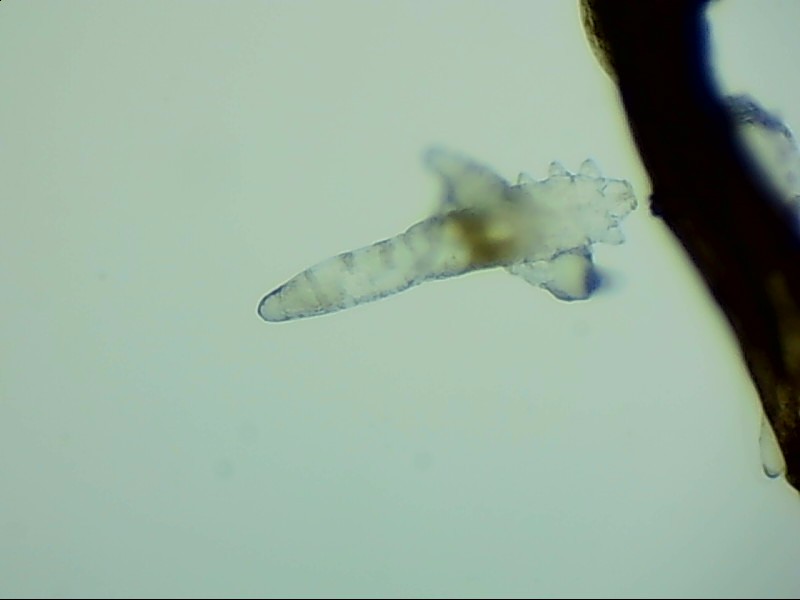

蠕形螨完全長(zhǎng)大也只有0.1-0.2毫米,因此肉眼難以看到它們,只有在電子顯微鏡下我們才能看到睫毛根部的一只只蠕形螨。這些螨蟲(chóng)每天都很活躍,且繁殖速度極快,完成一代生活史僅需大概15天。

螨蟲(chóng)無(wú)所遁形,螨蟲(chóng)鏡檢:

螨蟲(chóng)鏡檢主要是通過(guò)顯微鏡觀察,它能無(wú)死角放大你的睫毛,讓螨蟲(chóng)無(wú)處可躲。

在檢查的時(shí)候,醫(yī)生要在每個(gè)眼瞼上拔出幾根比較典型的睫毛,然后放在光學(xué)顯微鏡下,尋找有沒(méi)有螨蟲(chóng),同時(shí)觀察螨蟲(chóng)的數(shù)量多少。

如果任意一個(gè)眼瞼上螨蟲(chóng)數(shù)量較多,再加上你的眼睛有局部癥狀,后續(xù)就需要進(jìn)行相應(yīng)的治療了。